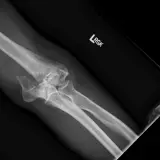

Over 2,100 interactive radiology cases, curated by radiologists for your level of training. Scroll, window, and view cases full screen — just like on PACS. Click linked findings in each writeup to jump straight to them on the image. Cases include sample reports, a focused discussion section, original illustrations, and videos.

完全交互式病例,配备您在 PACS 上期待的各项工具——滚动、调窗、缩放、平移、测量、ROI 和全屏模式。

丰富的标注直接在病例图像上突出关键发现。点击病例讲解中的关联发现,即可跳转至其在扫描上的精确位置。

像在工作站 PAC 上一样滚动、平移、调窗和缩放